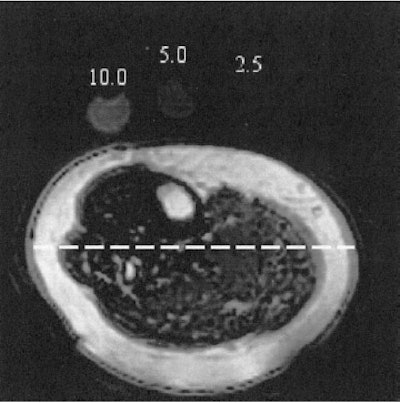

| A: Fat-selective MRI of the lower leg obtained by using spiral sequences and echo time of 5 ms. Lipid phantoms are visible near the top of the image. B: Histogram of pixel signal intensity covered by the dashed line in panel A across the image from left to right. Note the high lipid signal intensity in subcutaneous adipose tissue (1) and the relatively higher concentration of lipid within skeletal muscle on the right side of the image. Also note that the spike between 2 and 3 represents a section of the fatty septa (intermuscular adipose tissue), which is a potential confounder of muscle lipid content if regions of interest are not carefully drawn. Reproduced with permission by the American Journal of Clinical Nutrition. © Am J Clin Nutr 2004;79:748-754, Fig. 2A-B. American Society for Clinical Nutrition. |

A set of T1-weighted spin-echo sagittal images were acquired to localize phantoms and the lower limb. Another T1-weighted image was acquired to identify specific muscle groups, as well as subcutaneous and intermuscular adipose tissue. Fat-selective images were taken with a lipid phantom in every patient in order to produce lipids maps and quantify the lipid signal.

"The maps of lipid content were generated by using a spiral two-shot gradient-echo sequence to acquire images with different TEs," the authors explained. "These fat-selective images were acquired by placing a fat-suppression pulse at -440 Hz and following this pulse by a spectral-spatial radiofrequency excitation with a stop band at -440 Hz."

According to the results, "extremely good agreement was found between the fat signal intensity of the patients and the actual lipid concentration of standards...which were placed on the subject's leg during each scan." They found that the lipid content of the soleus (2.99 g/dL) and the medial head of the gastrocnemius (3.80 g/dL) were higher than that of the tibialis anterior (1.83 g/dL).

In addition, lipid content was more than two-fold higher (p<0.05) in the medial head of the gastrocnemius of obese subjects than in those of normal weight -- 5.48 g/dL versus 2.54 g/dL. However, there was no significant different in the tibialis anterior and soleus in both groups.